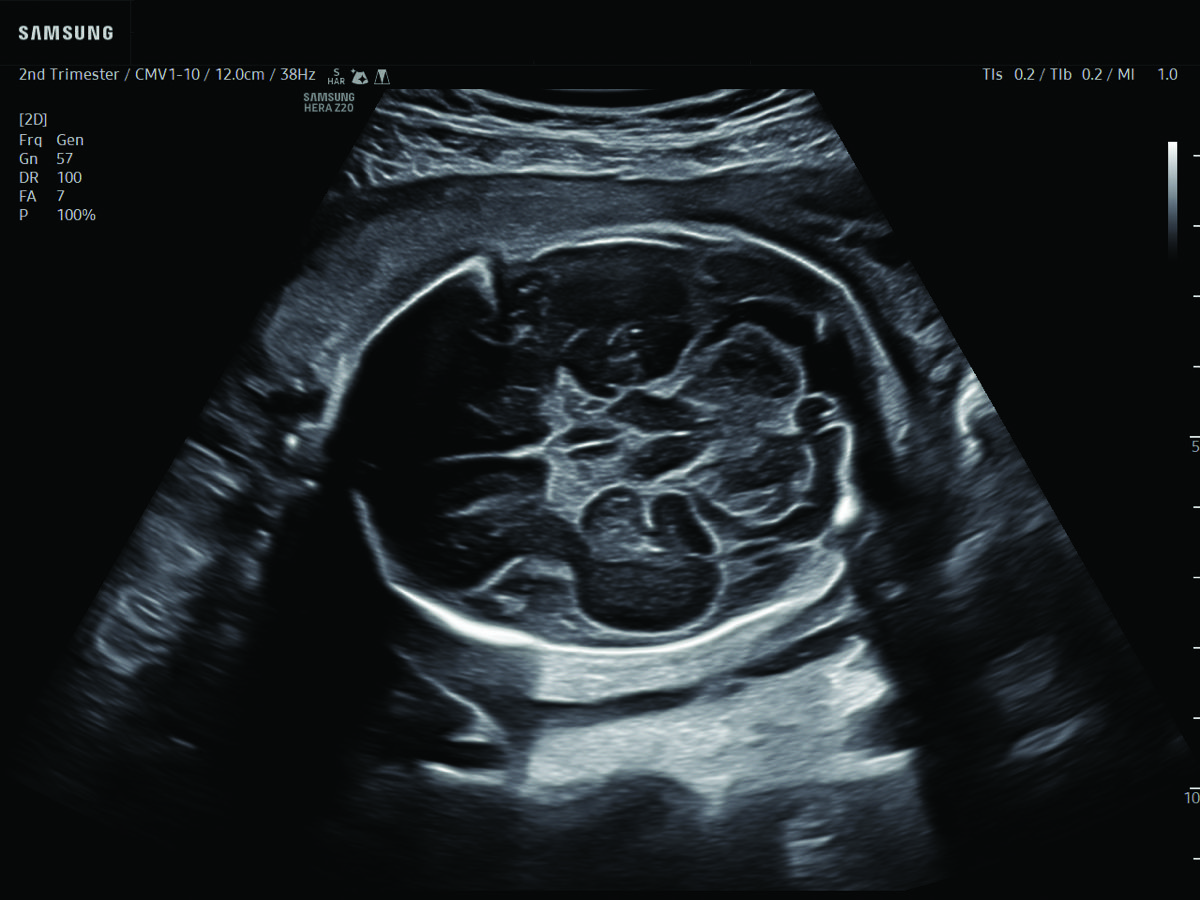

Comprehensive, advanced and expert MFM care for high-risk pregnancies

- Fetal anomalies